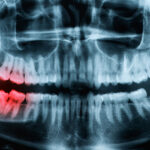

治療について 一覧 親知らずの抜歯 2023/03/06 治療について 親知らずとは、前歯の中心から数えて8番目にある歯のことです。 生えてくる人と生え ... ドライマウス 2023/03/06 治療について 気が付くと口の中が乾燥している… 朝起きたとき、食事をするときに気になったことは ... 歯ぎしり・食いしばり 2023/03/06 治療について 睡眠中、ギシギシ、ギリギリと音を立てて歯をすり合わせる「歯ぎしり」や、上下の歯を ... 顎関節症 2023/03/06 治療について 「顎が痛くて、硬いものが噛めない」 「口を大きく開けることができない」 「口を開 ... お問い合わせフォーム 2018/06/16 治療について, 医院について ※予約にあたって、必ずお読みください こちらの予約フォームからは、3日先のお日に ... « Previous 1 2